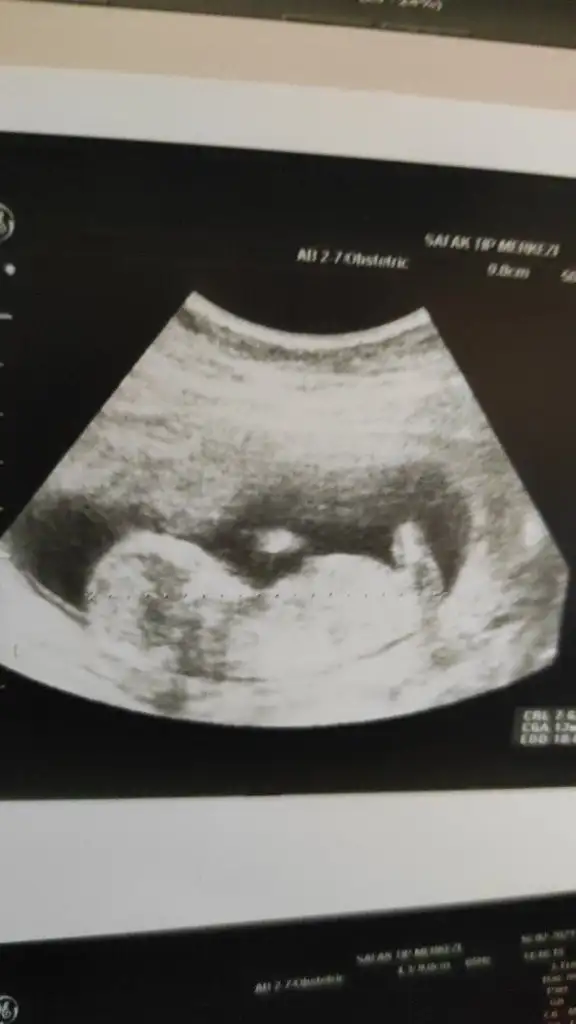

Ramzi Teorisi ve cinsiyet tahmini ( tutma olasılığı %85 miş )

Merhabalar bana da yorum yapar mısınız🤗 6. Ve 7. Hafta karindan ultrason fotolarimizi ekliyorum

Benim bebiş te 6+6iken karından Ultrason sizin tahmininiz nedir kızlar ☺️